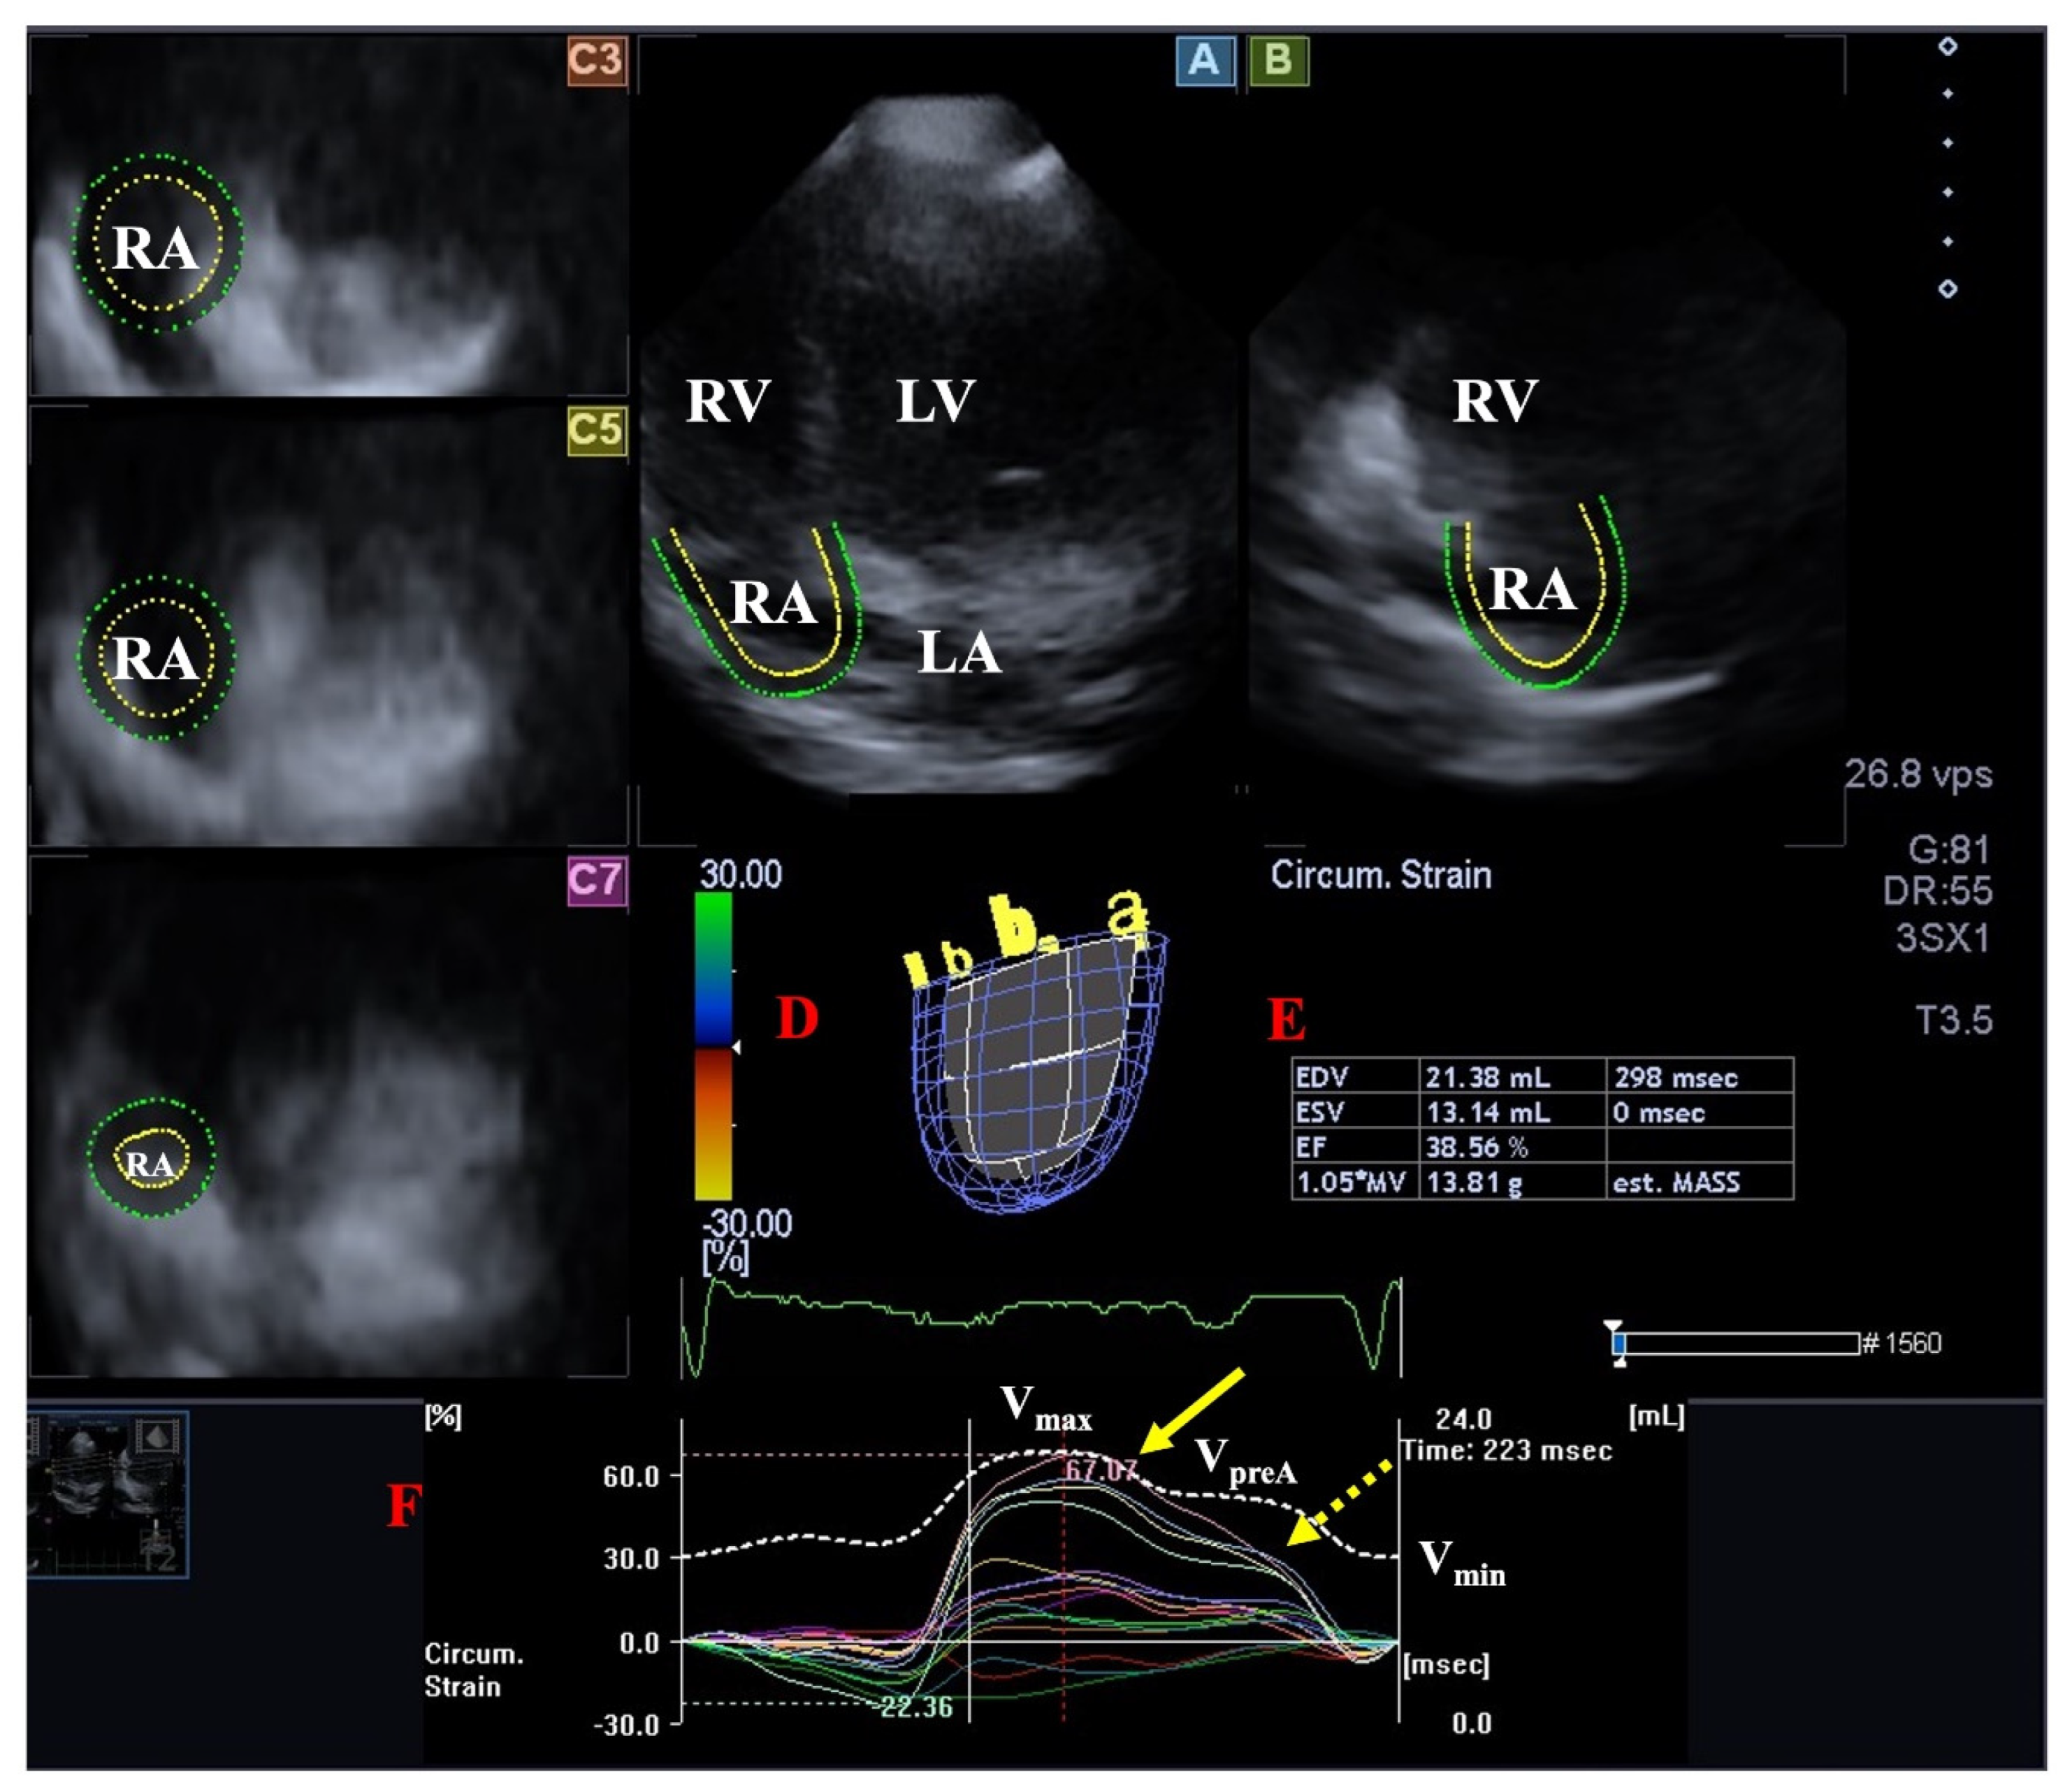

| LA emptying fractions were smaller and certain peak global LA strains were reduced. | [20] * | 12 | |

| Right atrium | RA volumes and certain stroke volumes were increased without RA strain abnormalities. | [19] * | 13 |